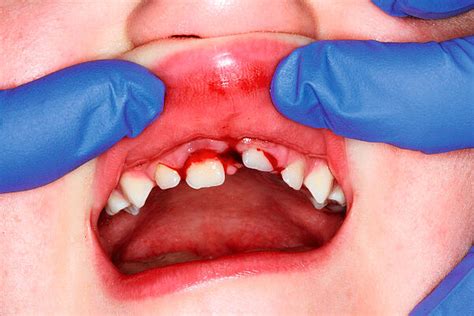

Zahnunfälle bei Kindern und deren Folgen

Zahnunfälle bei Kindern sind keine Seltenheit. Eine Erhebung der DGMKG ergab, dass sich fast jedes zweite Kind an den Zähnen verletzt. Am häufigsten betroffen sind die Schneidezähne von herumtobenden Kindern im Kindergartenalter. Durch das richtige Verhalten stehen die Chancen gut, dass Schäden in Grenzen gehalten und bleibende Zähne gerettet werden können.

Erste Hilfe nach Zahnunfall

Verletzungen im Mundraum sehen oft schlimm aus, da der menschliche Mund sehr stark durchblutet ist. Dennoch sollten auch vermeintlich harmlose Zahnunfälle nicht auf die leichte Schulter genommen werden. Gehen Sie in jedem Fall mit Ihrem Kind zum Zahnarzt! Bei Verletzungen, die den Mundraum betreffen, ist es wichtig, schnell zu handeln. Das Unfallopfer sollte sofort fest auf die Wunde beißen, um Blutungen zu stoppen. Neben dem Zahnfleisch können auch Lippen betroffen sein, die stark bluten. Eine Kompresse sollte daher von innen und außen auf die Wunde gedrückt werden. Eine aufgebissene Zunge ist bei Zahnunfällen nicht unüblich. Hier ist Vorsicht geboten: Versuchen Sie, die Zunge vorsichtig mit zwei Fingern aus dem Mund zu holen, idealerweise mit gewaschenen Fingern. Im Idealfall ist die Blutung nach fünf Minuten abgeklungen, und Sie können mit dem Kühlen beginnen. Grundsätzlich ist es immer ratsam, die betroffene Stelle zu kühlen, da Kälte die Gefäße zusammenziehen und weitere Blutungen verhindern kann. Kühlkompressen oder ein in kaltes Wasser getauchtues Tuch sind hierfür gut geeignet.

Ausgeschlagener Milchzahn

Suchen Sie zunächst den ausgeschlagenen Milchzahn und kontrollieren Sie, ob er mit oder ohne Zahnwurzel ausgeschlagen wurde. Untersuchen Sie den Mundraum nach Fragmenten und entfernen Sie diese. Vereinbaren Sie zeitnah einen Zahnarzttermin und nehmen Sie den ausgebrochenen Zahn mit. Es muss sichergestellt werden, dass der Milchzahn oder Fragmente davon nicht in den Kiefer gedrückt wurden. Ein Wiedereinsetzen des Milchzahns erfolgt in der Regel nicht, da die Gefahr, den Zahnkeim des bleibenden Zahnes zu schädigen, zu hoch ist.

Die erforderlichen Schritte hängen von der Größe des abgebrochenen Zahnes ab. Suchen Sie das fehlende Zahnfragment und nehmen Sie es zum Zahnarzt mit. Anders verhält es sich, wenn die abgebrochene Fläche größer ist und der Nerv betroffen ist oder sein könnte. Ist die Nervenkammer großflächig eröffnet, kann der Zahnarzt eine Milchzahn-Wurzelbehandlung durchführen. Verfärbt sich der Milchzahn innerhalb einer Woche dunkelgrau, ist das oft ein Hinweis auf einen Bluterguss im Zahn. In der Regel verheilt das Zahninnere innerhalb eines Monats wieder. Gelegentlich verfärbt sich der Milchzahn nach einem Sturz nur gelblich und hebt sich dadurch leicht von den umliegenden Zähnen ab. Liegt der Sturz Ihres Kindes schon eine längere Zeit zurück und der Zahn verfärbt sich z. B. gelblich, ist Vorsicht geboten, wenn sich mehrere Wochen nach einem Sturz eine Eiterblase bildet und der Zahn zunehmend zu wackeln beginnt.

Ein grauer Milchzahn: Ursachen und Maßnahmen

Ein plötzlich grau gewordener Milchzahn kann auf ein Trauma zurückzuführen sein, bei dem der Nerv abgestorben ist. Da Kinder schmerzunempfindlicher sind, tut der Zahn in der Regel nicht weh. Die graue Verfärbung muss nicht immer ein ernsthaftes Problem darstellen, da der Milchzahn später ausfällt. Dennoch ist es ratsam, einen Zahnarzt aufzusuchen, sobald die Graufärbung festgestellt wird.

Wenn der Zahn Ihres Kindes grau oder schwarz geworden ist, ist dies in den meisten Fällen die Folge eines Traumas. In den meisten Fällen erfordert ein grauer Zahn aufgrund eines Traumas keine dringende Behandlung, es sei denn, er wird schmerzhaft, löst sich oder zeigt Symptome einer Infektion.